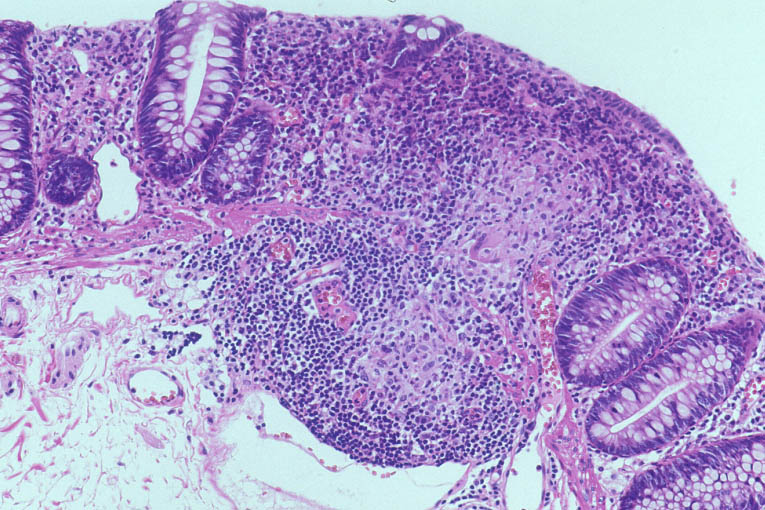

図11

慢性肉芽腫症の回腸末端部病変

右:HE染色

遺伝性好中球機能不全症である慢性肉芽腫症では、回腸末端部にクローン病類似の縦走潰瘍が形成される。組織学的に、粘膜~粘膜下層に壊死を欠く類上皮細胞肉芽腫が確認される。